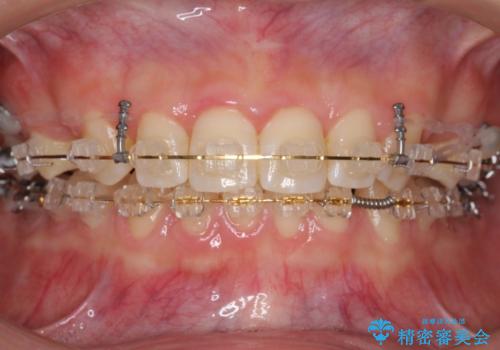

前歯のすきま 右上の小臼歯の垂直的骨吸収を抜歯で解決

- 審美装置

- 前歯のすきまを気にして来院。

奥歯が1歯対1歯で、過蓋咬合を呈していました。

レントゲンで、右上4番の近心の垂直的骨欠損があり、抜歯を行うこととしました。

それがなければ上顎歯列の遠心移動をすることで、非抜歯でマウスピース矯正でも可能であったと思います。

垂直的骨欠損は咬み合わせから起こったものと推察されました。

short faceであり、結果上顎の臼歯を近心に大きくロスさせることになったたため、非常に長く治療期間はかかりました。